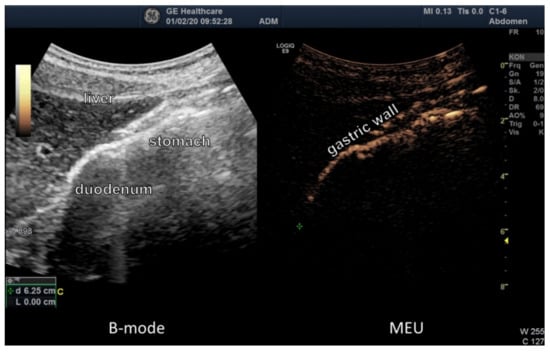

3.3. Ultrasound Examination of Intestinal Absorption